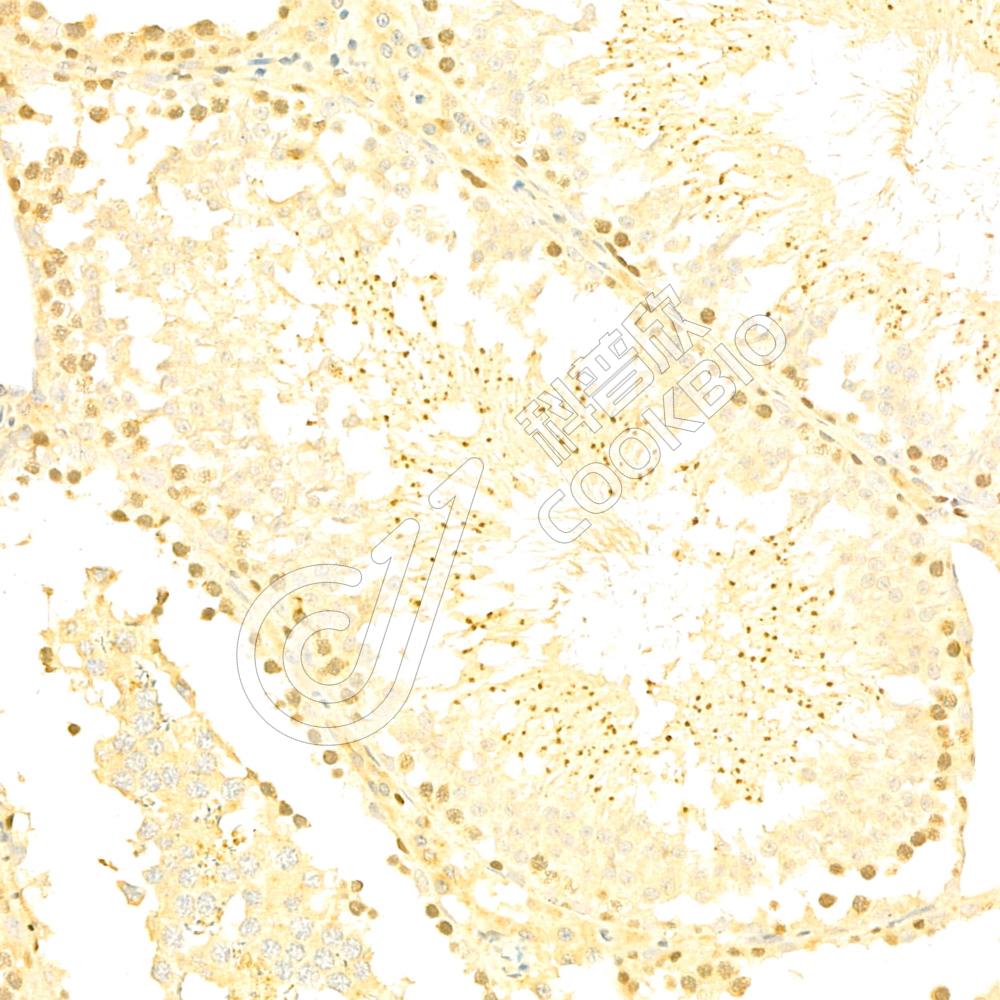

IHC检测COMMD4蛋白(货号 K1336852).

样品: 小鼠睾丸, 4%多聚甲醛 (货号KSG1101) 固定12-24小时.

抗原修复: Tris-EDTA抗原修复液(pH 9.0) (KSG1203), 98℃, 20分钟.

—抗: 1: 1900稀释, 4℃ 孵育过夜.

二抗: S-vision免疫组化多聚二抗(山羊抗兔),即用型 (货号KB3906), 室温孵育20分钟.

样品: 大鼠睾丸, 4%多聚甲醛 (货号KSG1101) 固定12-24小时.